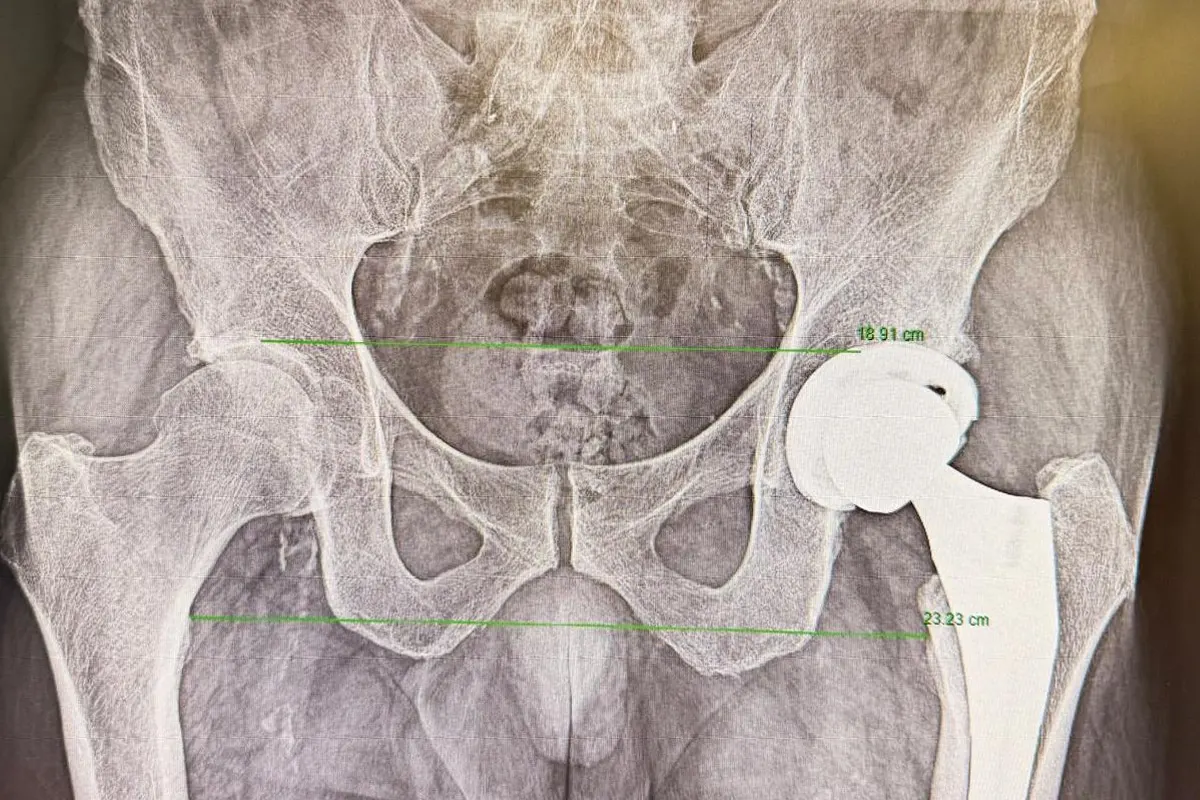

La otra clave que debería tranquilizar a los pacientes que se someten a una cirugía de prótesis de cadera se explica por la evolución de las técnicas quirúrgicas. La llamada vía anterior en la prótesis de cadera, aunque no es nueva, ha ganado popularidad en los últimos años por sus ventajas en el postoperatorio inmediato. A diferencia de otros abordajes, permite acceder a la articulación entre planos musculares, sin necesidad de seccionar músculos. “La gran ventaja de la vía anterior es que el paciente tiene menos dolor en los primeros momentos tras la cirugía y puede iniciar antes la movilización”, explica el doctor Martín Buenadicha. Esta menor agresión muscular favorece un inicio más temprano de la fisioterapia y de la marcha, elementos clave cuando se plantea un alta en el mismo día.